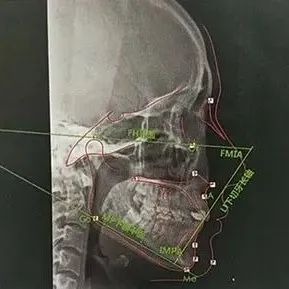

10分钟搞懂头影测量,临床实用干货分享

本文所述均是我学习归纳总结后筛选与临床实用息息相关的数据,不必纠结于搞懂头影测量所有数据的意义。引用张栋梁老师的话就是:理想是用来指引方向的,不是用来实践的。学过一点头影测量的会发现,有很多种测量方法,Downs和Steiner,还有国内的测量法等等。为什么会这样?因为没有一个测得完全准确的都只能作为参考,所以真的不用太纠结数据,注意临床实用性和患者主诉才是关键。那么具体如何看我相信大多数人第一眼见到这副图的时候都是一脸懵逼...